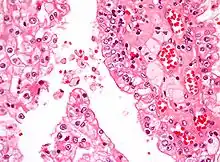

| Micrograph showing the most common type of kidney cancer (clear cell renal cell carcinoma). H&E stain. | |

The most common type of kidney malignancy is renal cell carcinoma,[34] which is thought to originate from cells in the proximal convoluted tubule of the nephron.[15][35] Another type of kidney cancer although less common, is transitional cell cancer (TCC) or urothelial carcinoma of the renal pelvis.[36] The renal pelvis is the part of the kidney that collects urine and drains it into a tube called the ureter.[36] The cells that line the renal pelvis are called transitional cells, and are also sometimes called urothelial cells. The transitional/urothelial cells in the renal pelvis are the same type of cells that line the ureter and bladder. For this reason TCC of the renal pelvis is distinct from RCC and is thought to behave more like bladder cancer.[36] Other rare types of kidney cancers that can arise from the urothelial cells of the renal pelvis are squamous cell carcinoma and adenocarcinoma.[15]

Renal cell carcinoma has been further divided into sub-types based on histological features and genetic abnormalities. The 2004 WHO Classification of the Renal Tumors of the Adults describes these categories:[40]

- Clear cell RCC